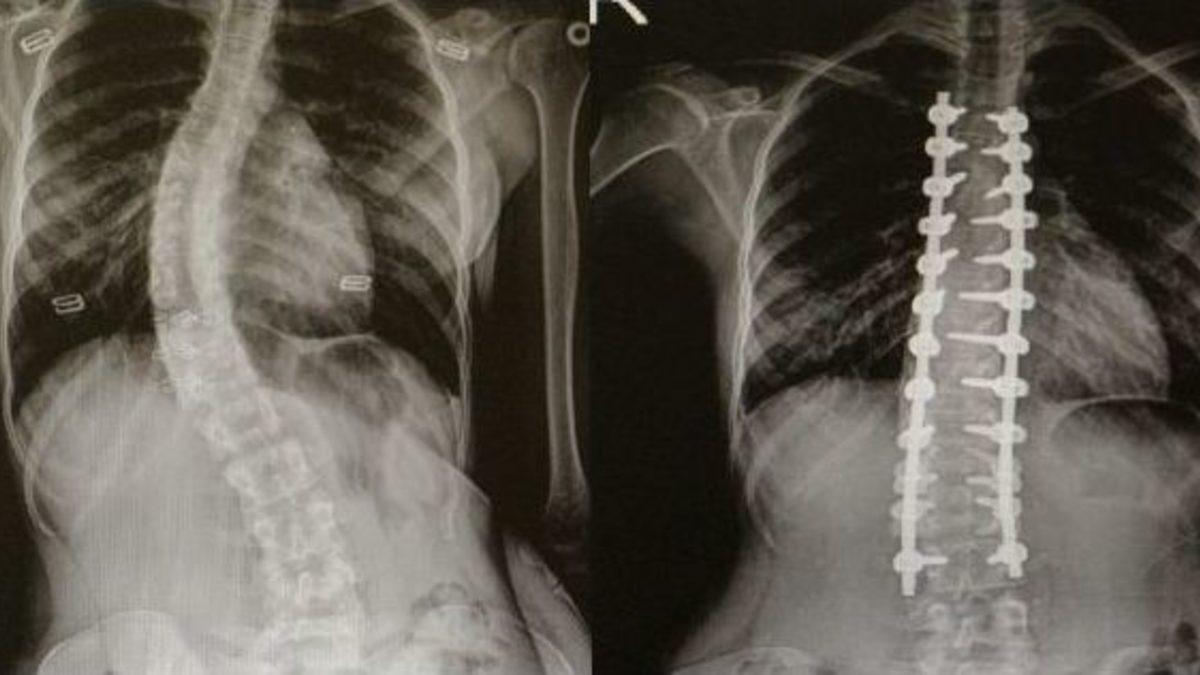

Skolyoz(omurga eğriliği) olan hastalar Ondokuz Mayıs Üniversitesi(OMÜ) Tıp Fakültesi’nde şifa buluyor.Skolyozun genellikle çocuklarda görülen bir hastalık olduğunu ifade eden OMÜ Tıp Fakültesi Ortopedi ve Travmatoloji Anabilim Dalı Öğretim Üyesi Yrd. Doç. Dr. Mesut Kılıç, omurga eğriliği olan hastaların OMÜ Tıp Fakültesi’nde rahatlıkla tedavi edildiğini söyledi. Skolyoz cerrahisinde modern tekniklerin kullanıldığını belirten Kılıç, nöromonitörizasyon uygulamasıyla felç riskini yüzde sıfıra kadar indirdiklerini söyledi.Kılıç: "Bazı hastalarda cerrahi tedavi gerektirmektedir"Skolyozun özellikle kız çocuklarda daha sık görülen bir durum olduğunu söyleyen Yrd. Doç. Dr. Mesut Kılıç, "Skolyoz hastalığı özellikle çocuklarda ve gençlerde gerek kozmetik gerekse fonksiyonel açıdan şikayetlere sebep oluyor. Tedavide çoğunlukla cerrahi dışı yöntemler uygulanır. Korse, egzersiz gibi. Fakat bazı hastalarda cerrahi tedavi gerektirmektedir. Cerrahide günümüzde modern teknikler kullanılmaktadır. Halk arasında platin diye bilinen uygulamalarla düzeltme sağlanmaktadır. Ayrıca son dönemlerde teknolojik gelişmelerle ortaya çıkan nöromonitörizasyon dediğimiz bir sistem uygulanıyor. Hasta uyutularak bilgisayara bağlanıyor. Ameliyat sırasında bir felç durumu var mı yok mu? Sinir yapılarında bir zedelenme var mı yok mu bunu bize bildiriyor. Halk arasında bu tür ameliyatlarda ’felç olursunuz’ korkusunu biz çok duyuyoruz. Fakat bu uygulama ile felç riskini yüzde sıfıra yakın indiriyoruz" dedi.Yavuz: "Artık dayanamıyordum"Skolyoz ameliyatı olan Sedef Yavuz(17), "Omurgam yavaş yavaş sağ tarafa doğru dönmeye başlamıştı. Ağrılarım oluyordu. Artık dayanamıyordum. Oturduğumda ve yürüdüğümde bunalmaya başlamıştım. Tedavimin nerede yapılabileceğini araştırdım ve OMÜ’de bu tedavinin yapıldığını öğrendim. Doktorumla konuştuk ve ameliyat olmaya karar verdim. Ameliyata gülerek girdim. Ameliyattan sonra biraz ağrılarım oldu ama şimdi çok iyiyim" diye konuştu.